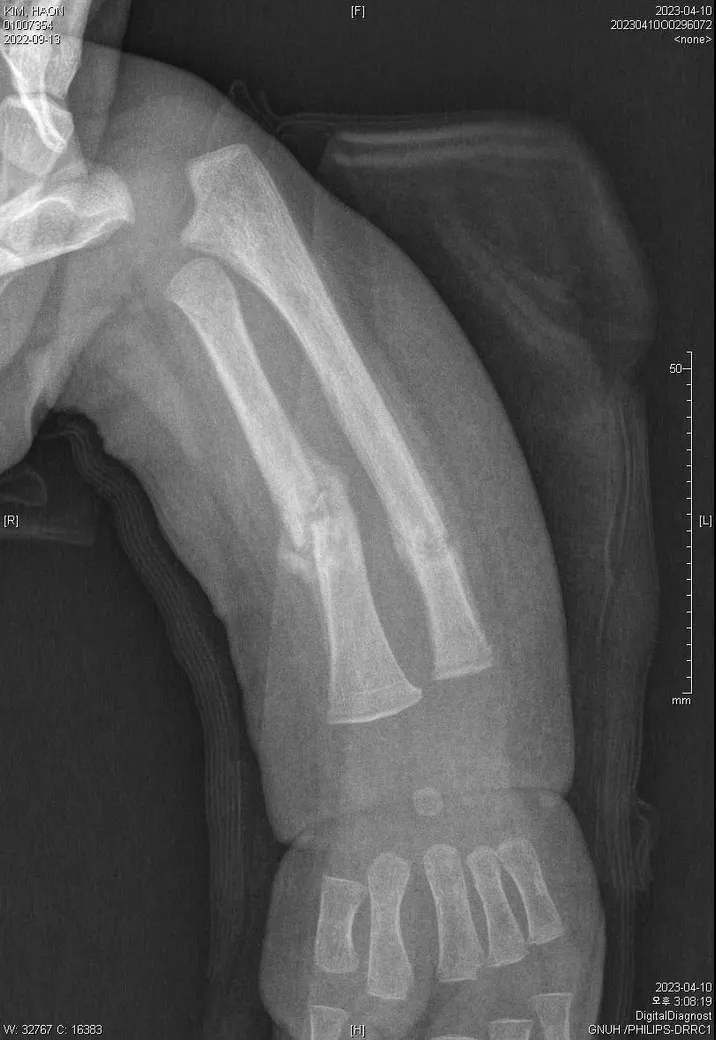

다름이 아니라, 첨부드린 엑스레이(X-ray) 사진처럼 골절 사실을 알게 되고 골절 발생 시점 대략적으로나마 추정시기를 파악하려고 문의 드리게 되었습니다

1) 3월 30일 촬영한 X-ray만으로 정확한 골절 시기를 100% 특정하는 데에는 한계가 있다는 점 충분히 인지하고 있기에 촬영날짜 기준으로 대략적으로 어느정도 시점에서 발생되었을 것으로 추측(ex 당일, 7~10일전, 7~14일 전, 10일 ~ 20일전, 14일 ~ 30일전 등등등)되는지 이해하고 싶습니다.

첨부드린 파일에도 있지만 4월 10일 사진에서는 유합 직전의 상당량의 켈로스 라는 것이 발견된다고 합니다.

• 2번 째 사진

보호자분이 원하시는 것은 2023-03-30에 골절이 된 사진만 가지고 언제 골절이 되었는지 추정을 하고 싶다는 말씀이죠? 3번째 사진에서 주변살들이 많이 부어있거나 하지 않아서 시간이 어느 정도 지난 것으로 보이네요. 초기유합은 1-2개월 정도 걸리는 것으로 알려져 있는 것으로 알려져 있으니 그 정도를 생각할 수 있을 것 같네요. 추정일 뿐입니다.